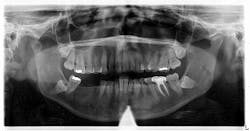

A panoramic radiograph revealed an almost-vague radiodense lesion on the lower left side, around the apices of teeth nos. 20–22, measuring approximately 3 cm x 1.5 cm. The lesion was nonpalpable, the area was not tender to palpation, and the patient was unaware of its presence.

- These sclerotic areas may remain unchanged for years (even after successful treatment of associated infected teeth), may partially resolve, or may completely disappear (and regions become radiographically normal again). Serial radiographs showing any increases in size indicate an active lesion.

Since this patient presented with no neurosensory changes, cortical expansion or displacement or resorption of adjacent teeth, and its cause could not be readily explained, it is consistent with a diagnosis of idiopathic osteosclerosis. The patient continues to be recalled periodically to assess for changes in this area.